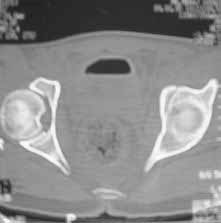

Male 22 yrs of age, RTA, front seat passenger in a truck. Sustained grade IIIB fracture of Tibia, and a Posterior dislocation of the Ipsilateral Left Hip.

Emergent closed reduction performed, and Tibial wound debrided. Next day Exfix applied and fibula plated. Initially femoral head fracture was not appreciated and it was thought that this is a posterior wall fracture. Presently two weeks down the line, Tibial wound is better but not completely healthy. and plastics want to wait for another five days, before they flap it. I enclose radiographs, Judet view, Ct scans in this and following mails.

Based on the selected images that you shared with us, I would not leave it as is. The fragment is significant in terms of its size and location and displacement.